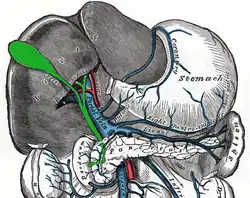

The common hepatic duct is the first part of the biliary tract.[2] It is formed by the union of the right hepatic duct (which drains bile from the right functional lobe of the liver) and the left hepatic duct (which drains bile from the left functional lobe of the liver).[3] It ends by uniting with the cystic duct (coming from the gallbladder) to form the bile duct.[4]

The common hepatic duct typically unites with the cystic duct some 1-2cm superior to the duodenum and anterior to the right hepatic artery, with the cystic duct approaching the common hepatic duct from the right.[4]

The right branch of the hepatic artery proper usually passes posterior to the duct, but may rarely pass anterior to it instead.[5]

The common hepatic duct is an important anatomic landmark during surgeries such as cholecystectomy. It forms one edge of Calot's triangle, along with the cystic duct and the cystic artery. All constituents of this triangle must be identified to avoid cutting or clipping the wrong structure.